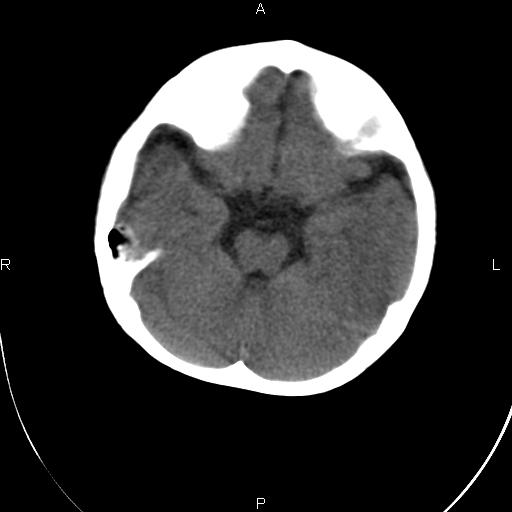

标题: PED1851:患儿,一岁半。癫痫样抽搐三个月。

家属诉三个月前曾有发热体温达39以上,鼻塞流涕,伴抽搐。治疗后发热等症状消失,偶有抽搐,近几日抽搐频繁。小儿不怎么会看,请老师们指教。

双侧额颞部硬模下积液征,建议除外脑膜炎检查

脑外间隙积液,局部脑回受压,脑沟变浅,支持考虑硬膜下积液,建议增强看是否有脑膜强化

另右侧裂似乎明显较左侧长\\宽,不完全除外脑裂畸形

双侧额颞叶发育不良,脑外间隙增宽